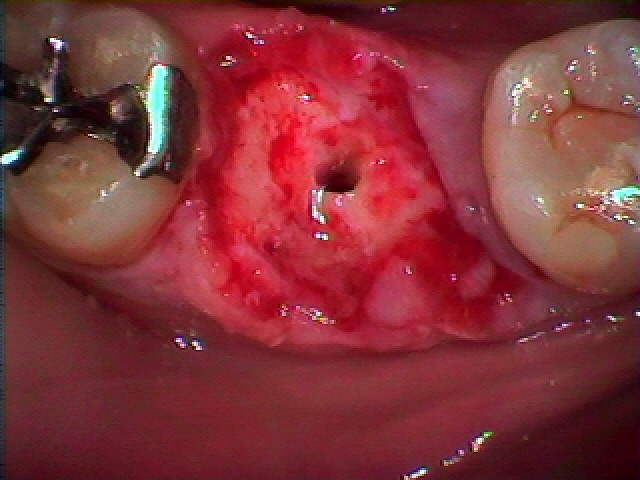

インプラント窩を形成しています